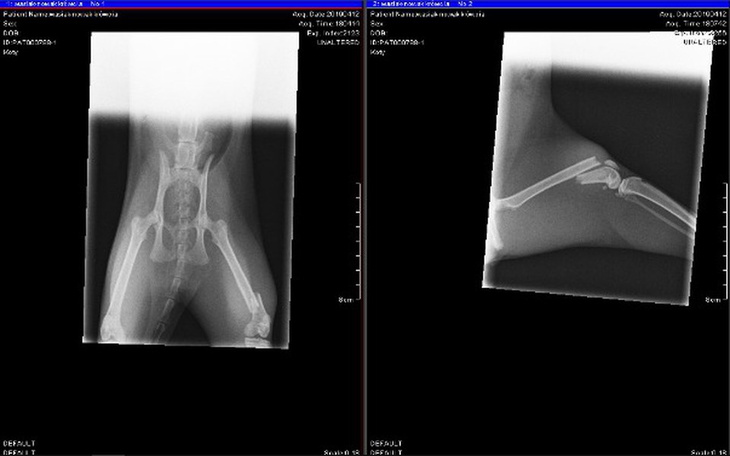

Edit: Witajcie kochani, nasza mała Krówcia przeszła pomyślnie operacje. Jak widać na zdjęciu gwóźdź podtrzymuje kość, a Kotek spędza 4 tygodnie w klatce kennelowej. Według lekarza wszystko zrasta się prawidłowo i nie ma powodów do obaw, pomimo że była groźba, że może to się nigdy nie zrosnąć. Krówka nadal musi być pod kontrolą weterynarza i za 2 tygodnie odbędzie się kolejna wizyta. Niestety nadal potrzebujemy wsparcia finansowego, gdyż zapożyczyliśmy się, aby wykonać operacje.